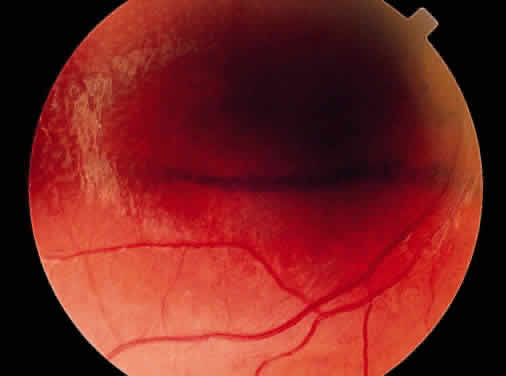

Clinically, retinal schisis presents with decreased central visual acuity, absolute scotomas, or both.1,33,38 Children may have strabismus and nystagmus.25,47 As in FEVR, but in contrast to Wagner and Stickler syndrome, the refraction tends to be hypermetropic (“hypermetropic amblyopia”).1,25,26,31–34,40,48 On biomicroscopic examination, edema and cystic central macular schisis of the retina are apparent in virtually all cases.37,38 Loss of macular reflex, which may be an early sign,34,35 is followed by wheel-like formation,37 a multicystic radiate appearance (Fig. 1),38 pigmentary degeneration, and cystic macular atrophy (Fig. 2).38 These macular changes, not bullous schisis per se, determine visual loss in patients often in the fourth or fifth decade of life.51